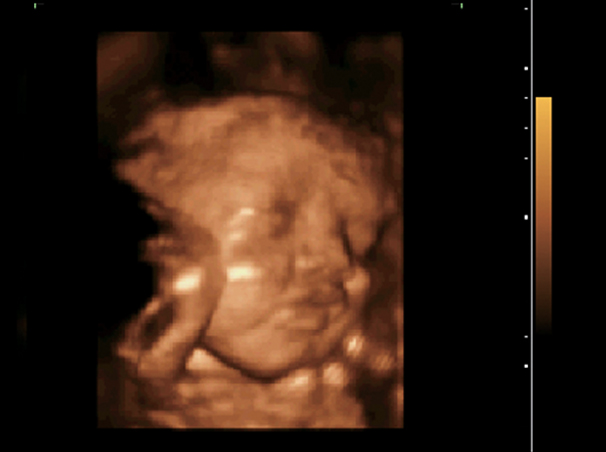

29 Weeks Fetal Face, 4D Mode